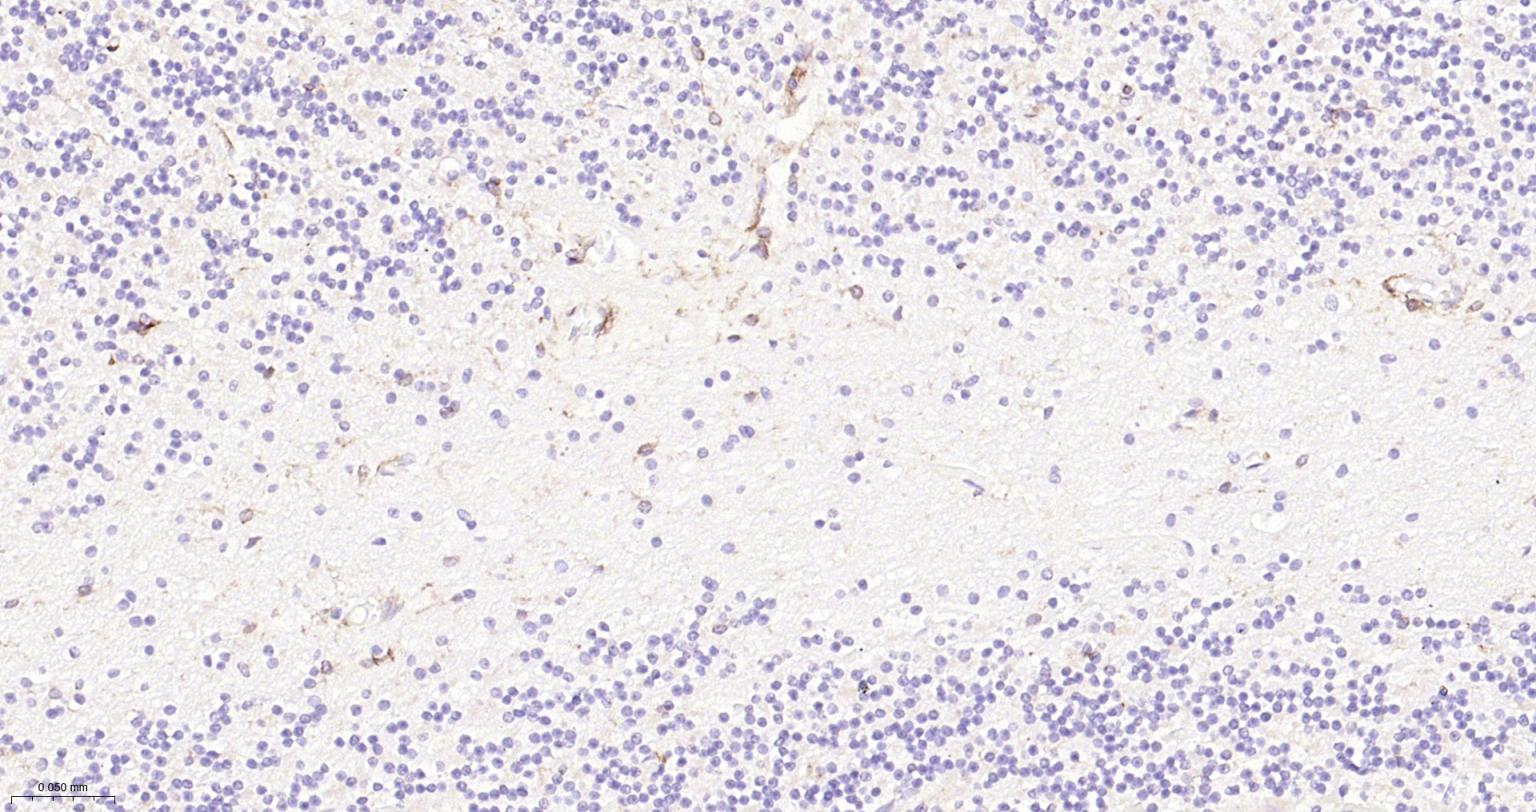

Immunohistochemical analysis of paraffin embedded human cerebellum tissue slide using IHC0298H (Human CD11b IHC Kit).